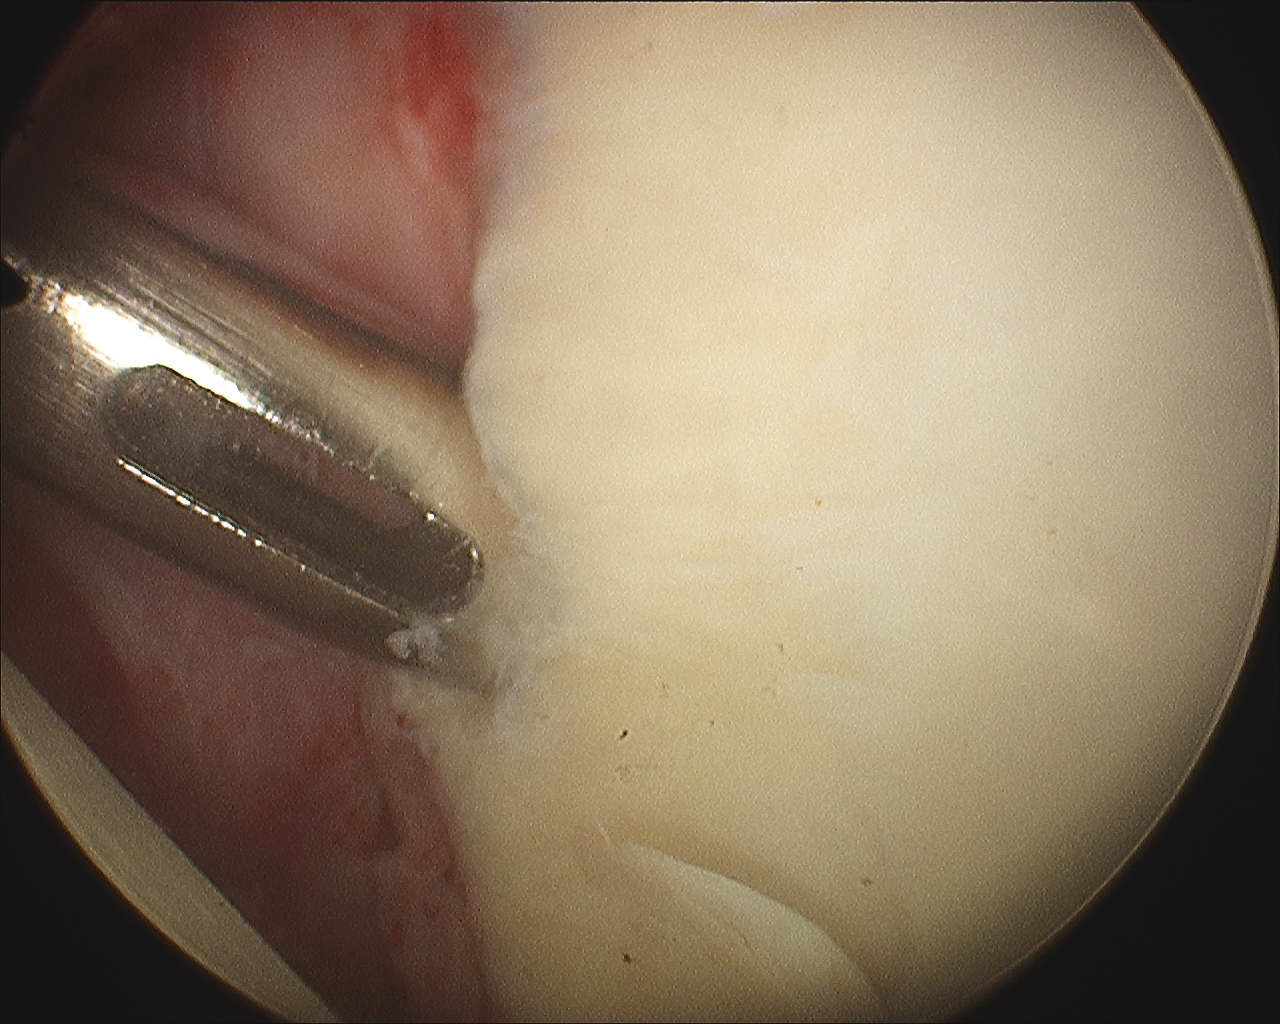

Debride anterior glenoid bone to bleeding bone

Shoulder Arthroscopy Bony Bankart

Insert anchors

Inferior anchor at 5.30 o'clock

- curved anchor guide / trans-subscapularis

- on rim of glenoid

Other anchors typically at 3 and 4 o'clock